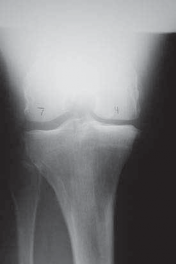

5. Radiographic evaluation in planning for an HTO is of paramount importance. Routine radiographs to obtain include bilateral anteroposterior (AP) standing, bilateral posteroanterior (PA) 45-degree flexed (ie, skier’s view), lateral view of affected knee, and bilateral Merchant views.

1. The AP standing and PA 45-degree flexed views allow the determination and initial grading of medial or lateral joint space narrowing. Joint space narrowing often can be found at the posterior condylar area and, therefore, may be missed on a routine AP standing knee radiograph.

1. Flexing the knee to 45 degrees allows a different area of the femoral condyle to be evaluated tangentially by the xray beam and may reveal significant arthritic change (

FIG 2A,B

).

2. The lateral view allows initial assessment of the patellofemoral joint and the determination of tibial slope.

3. The Merchant views complete the patellofemoral joint evaluation and assess the patellofemoral joint for arthritic changes.

4. Further radiographic evaluation includes a mechanical axis view (hip-knee-ankle). This view makes it possible to determine initial varus and valgus alignment of the bilateral lower extremities and the overall mechanical axis, and to

template correction angles for the opening wedge HTO (

FIG 2C

FIG 2 • A. AP radiograph of the right knee showing significant narrowing of the medial joint space with flattening of the medial femoral condyle and osteo-phyte formation. B. PA 45-degree flexed view (ie, Rosenberg view) of the same knee is obtained to show a different tangential view of the condyles. In this view, the patient has cartilage space remaining, but the medial compartment is narrowed. The numbers written in the condyles represent millimeters of joint space. C. Mechanical axis view of the bilateral lower extremities shows severe bilateral varus deformities of the lower extremity. Although the picture is underpenetrated toward the femoral heads, the steps for obtaining the mechanical axis are as follows: (1) Mark the center of the femoral head. (2) Mark the center of the ankle. (3) Draw a straight line between them (ie, the most medial line on the illustration). If the line is medial to the center of

the knee, then the patient is in varus. If it is lateral,

the patient is in valgus. In this case, the patient is in severe varus.